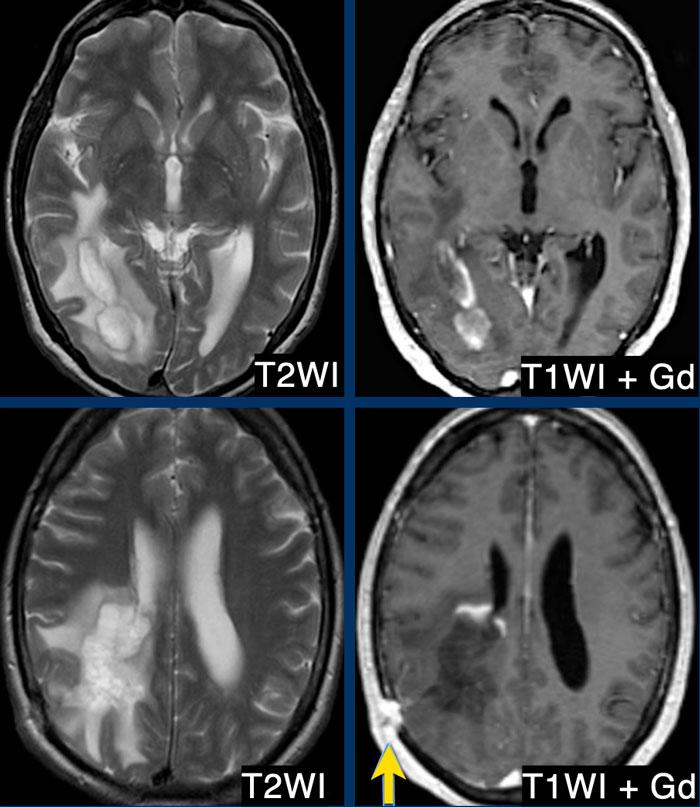

Đây là các hình ảnh chuỗi xung T2W và T1W sau tiêm thuốc tương phản từ của một nam bệnh nhân 39 tuổi nhập viện với bán manh khởi phát bán cấp.

Bệnh nhân được chỉ định sinh thiết để phân biệt giữa u thần kinh đệm và bệnh mất myelin.

Có một khối trong nhu mô não ở thùy thái dương và thùy chẩm phải với viền giảm tín hiệu trên T2, chỉ ngấm thuốc một phần (dấu hiệu vòng nhẫn hở) trên các hình ảnh sau tiêm thuốc tương phản từ.

Có phù nề xung quanh nhưng hiệu ứng khối tương đối ít.

Đây là tổn thương mất myelin được xác nhận qua sinh thiết.

Dạng ngấm thuốc vòng nhẫn hở kết hợp với viền giảm tín hiệu T2 và lưu lượng máu não (CBF) thấp đều là các dấu hiệu gợi ý bệnh mất myelin.